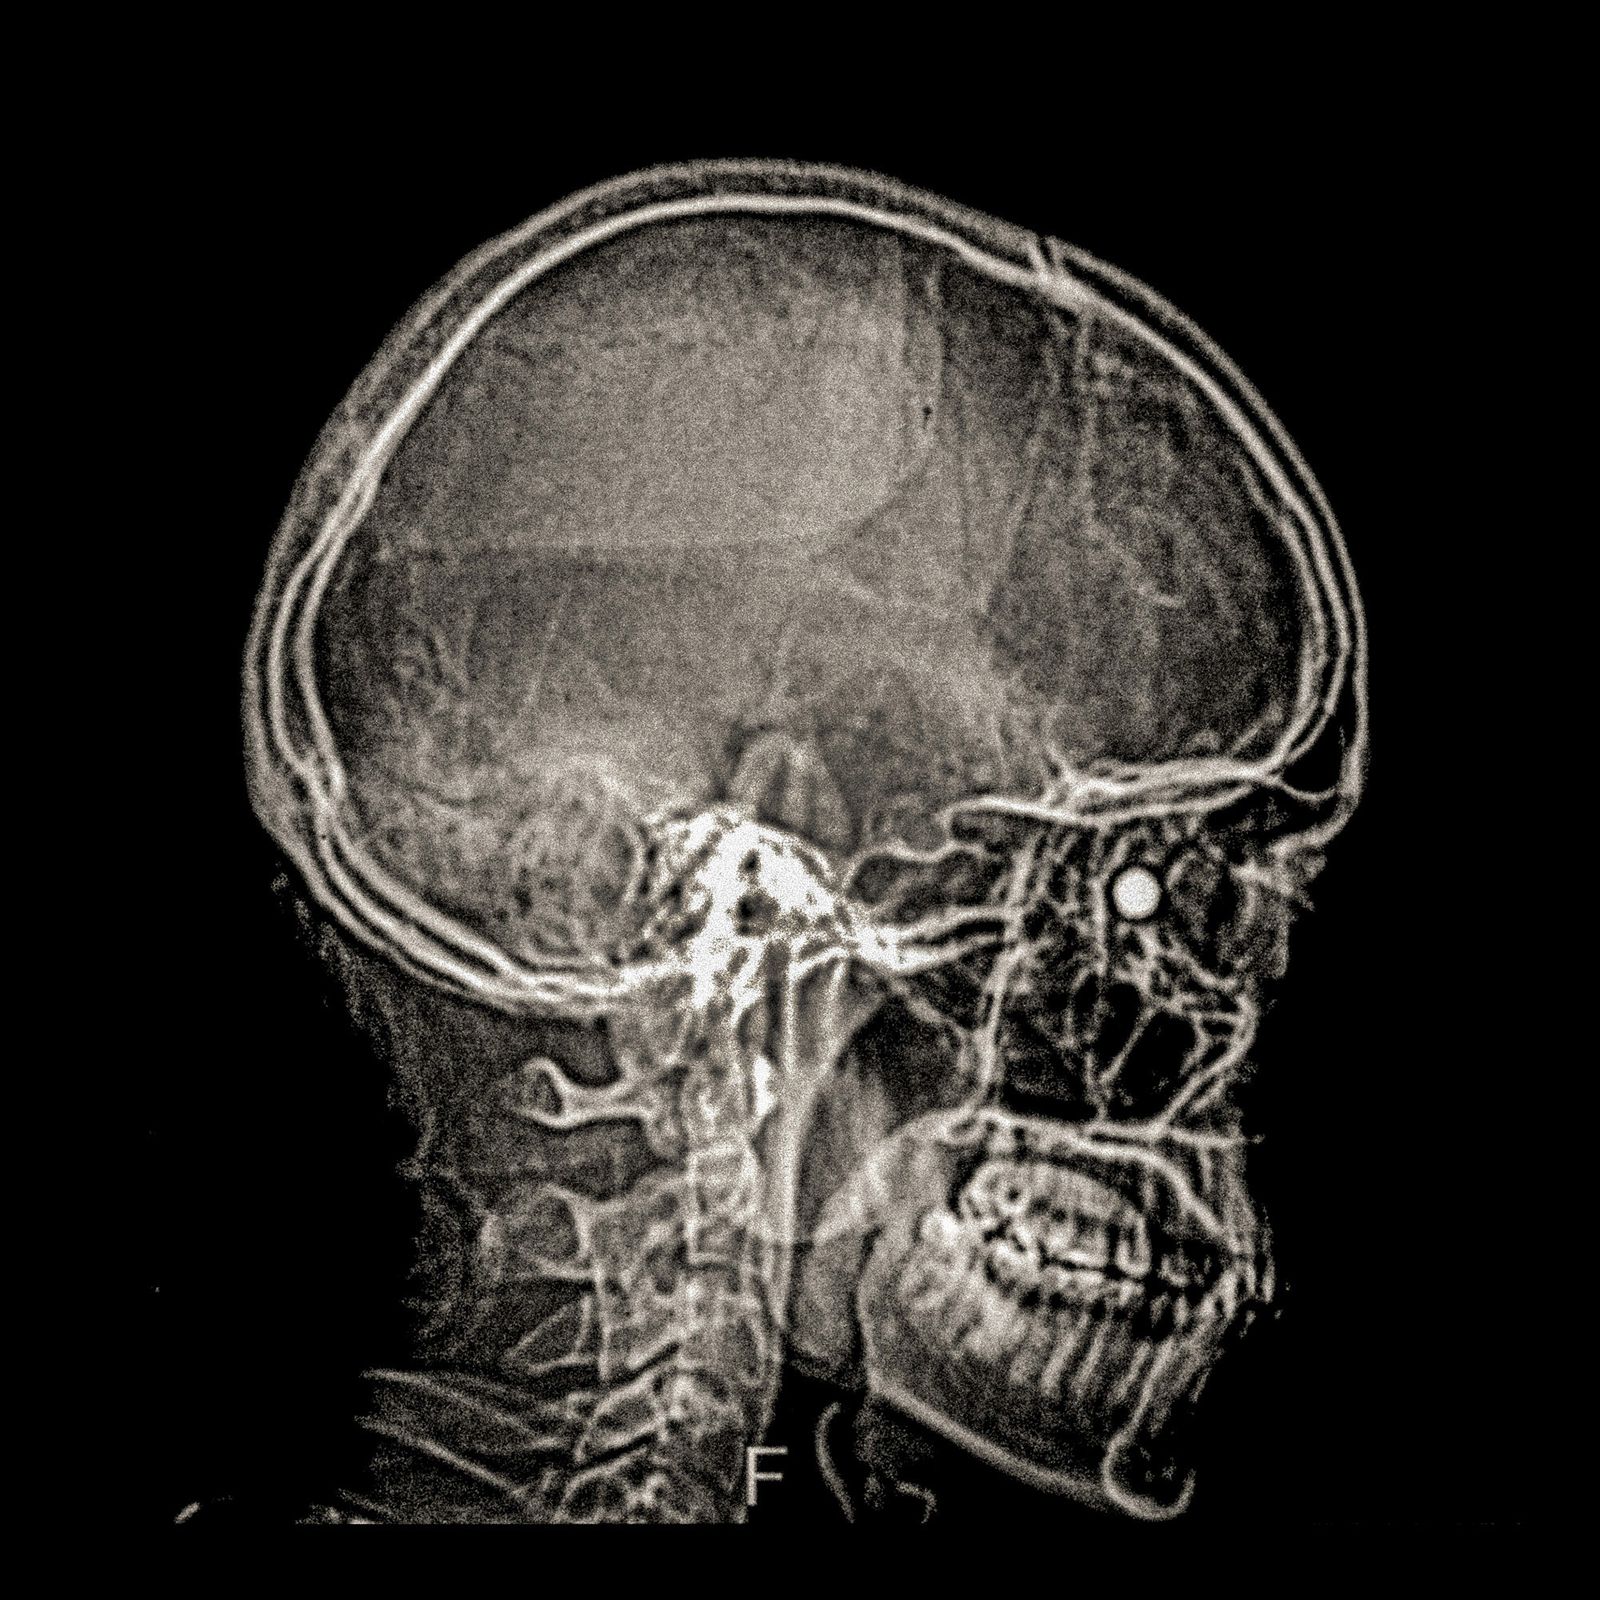

X-ray of Fabiola Campillai's face after she received a direct hit from a tear gas bomb fired by the carabineros chilean police, that caused her to lose both eyes.